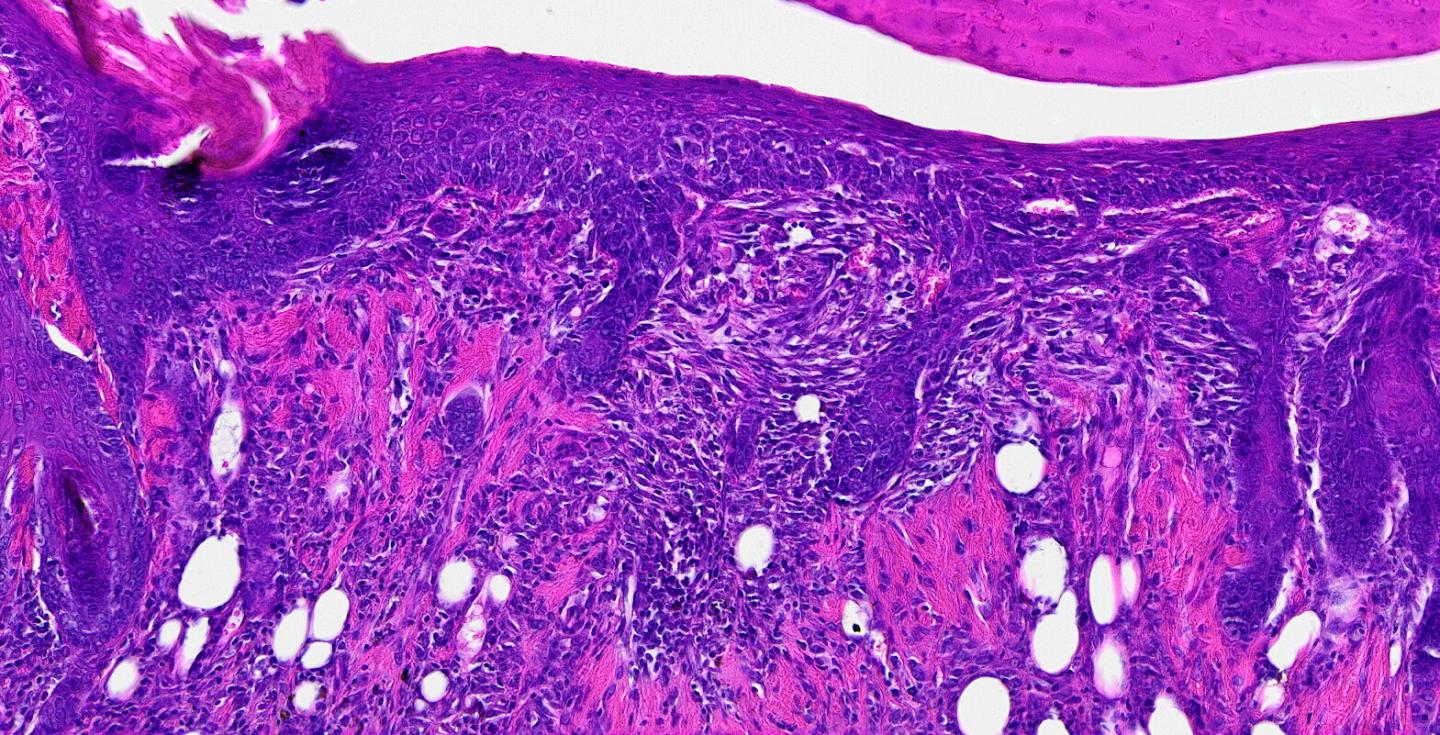

image: This is a tissue section 14 days post-wounding reveals the presence of hair follicles regenerating at the center of the wound. Re-growing hair follicles is one of the biggest challenges in the field of wound healing.

The researchers also demonstrated that wounds treated with the fibronectin dressing have close to normal epidermal thickness and dermal architecture, and even regrew hair follicles -- often considered one of the biggest challenges in the field of wound healing.

"This is an important step forward," said Chantre. "Most work done on skin regeneration to date involves complex treatments combining scaffolds, cells and even growth factors. Here we were able to demonstrate tissue repair and hair follicle regeneration using an entirely material approach. This has clear advantages for clinical translation."